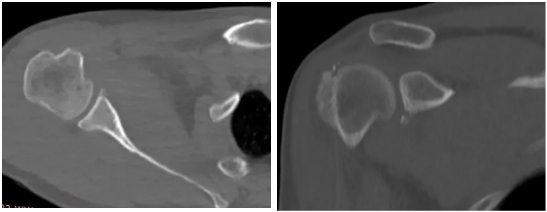

病例1

病史摘要:男性,44歲,跌傷致右肩關(guān)節(jié)疼痛數(shù)天,活動不利。

CT圖示:右側(cè)肱骨后外上方局部骨皮質(zhì)塌陷,連續(xù)性中斷(箭頭);肩胛盂前下份邊緣變鈍,見高密度分離小骨片影(三角形)。